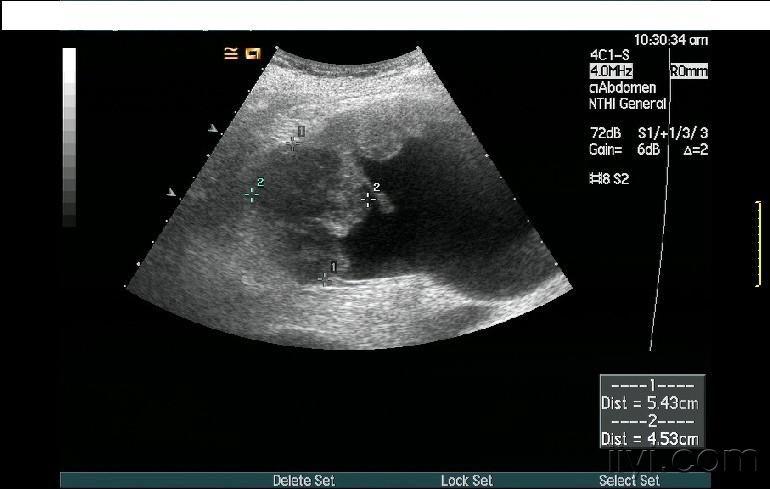

肾盂旁囊肿超声

肾盂旁囊肿超声,肾盂旁囊肿

肾盂旁囊肿